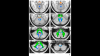

The Cerebellar White Matter Atlas is based on probabilistic tractography of high resolution, high quality diffusion MR data of 90 healthy subjects from the Human Connectome Project database. The atlas comes as a 3D probabilistic map, as well as binary parcellations at different probability thresholds. MNI - as well as SUIT (Spatially Unbiased Infratentorial Template) - compatible versions of the atlas are provided.